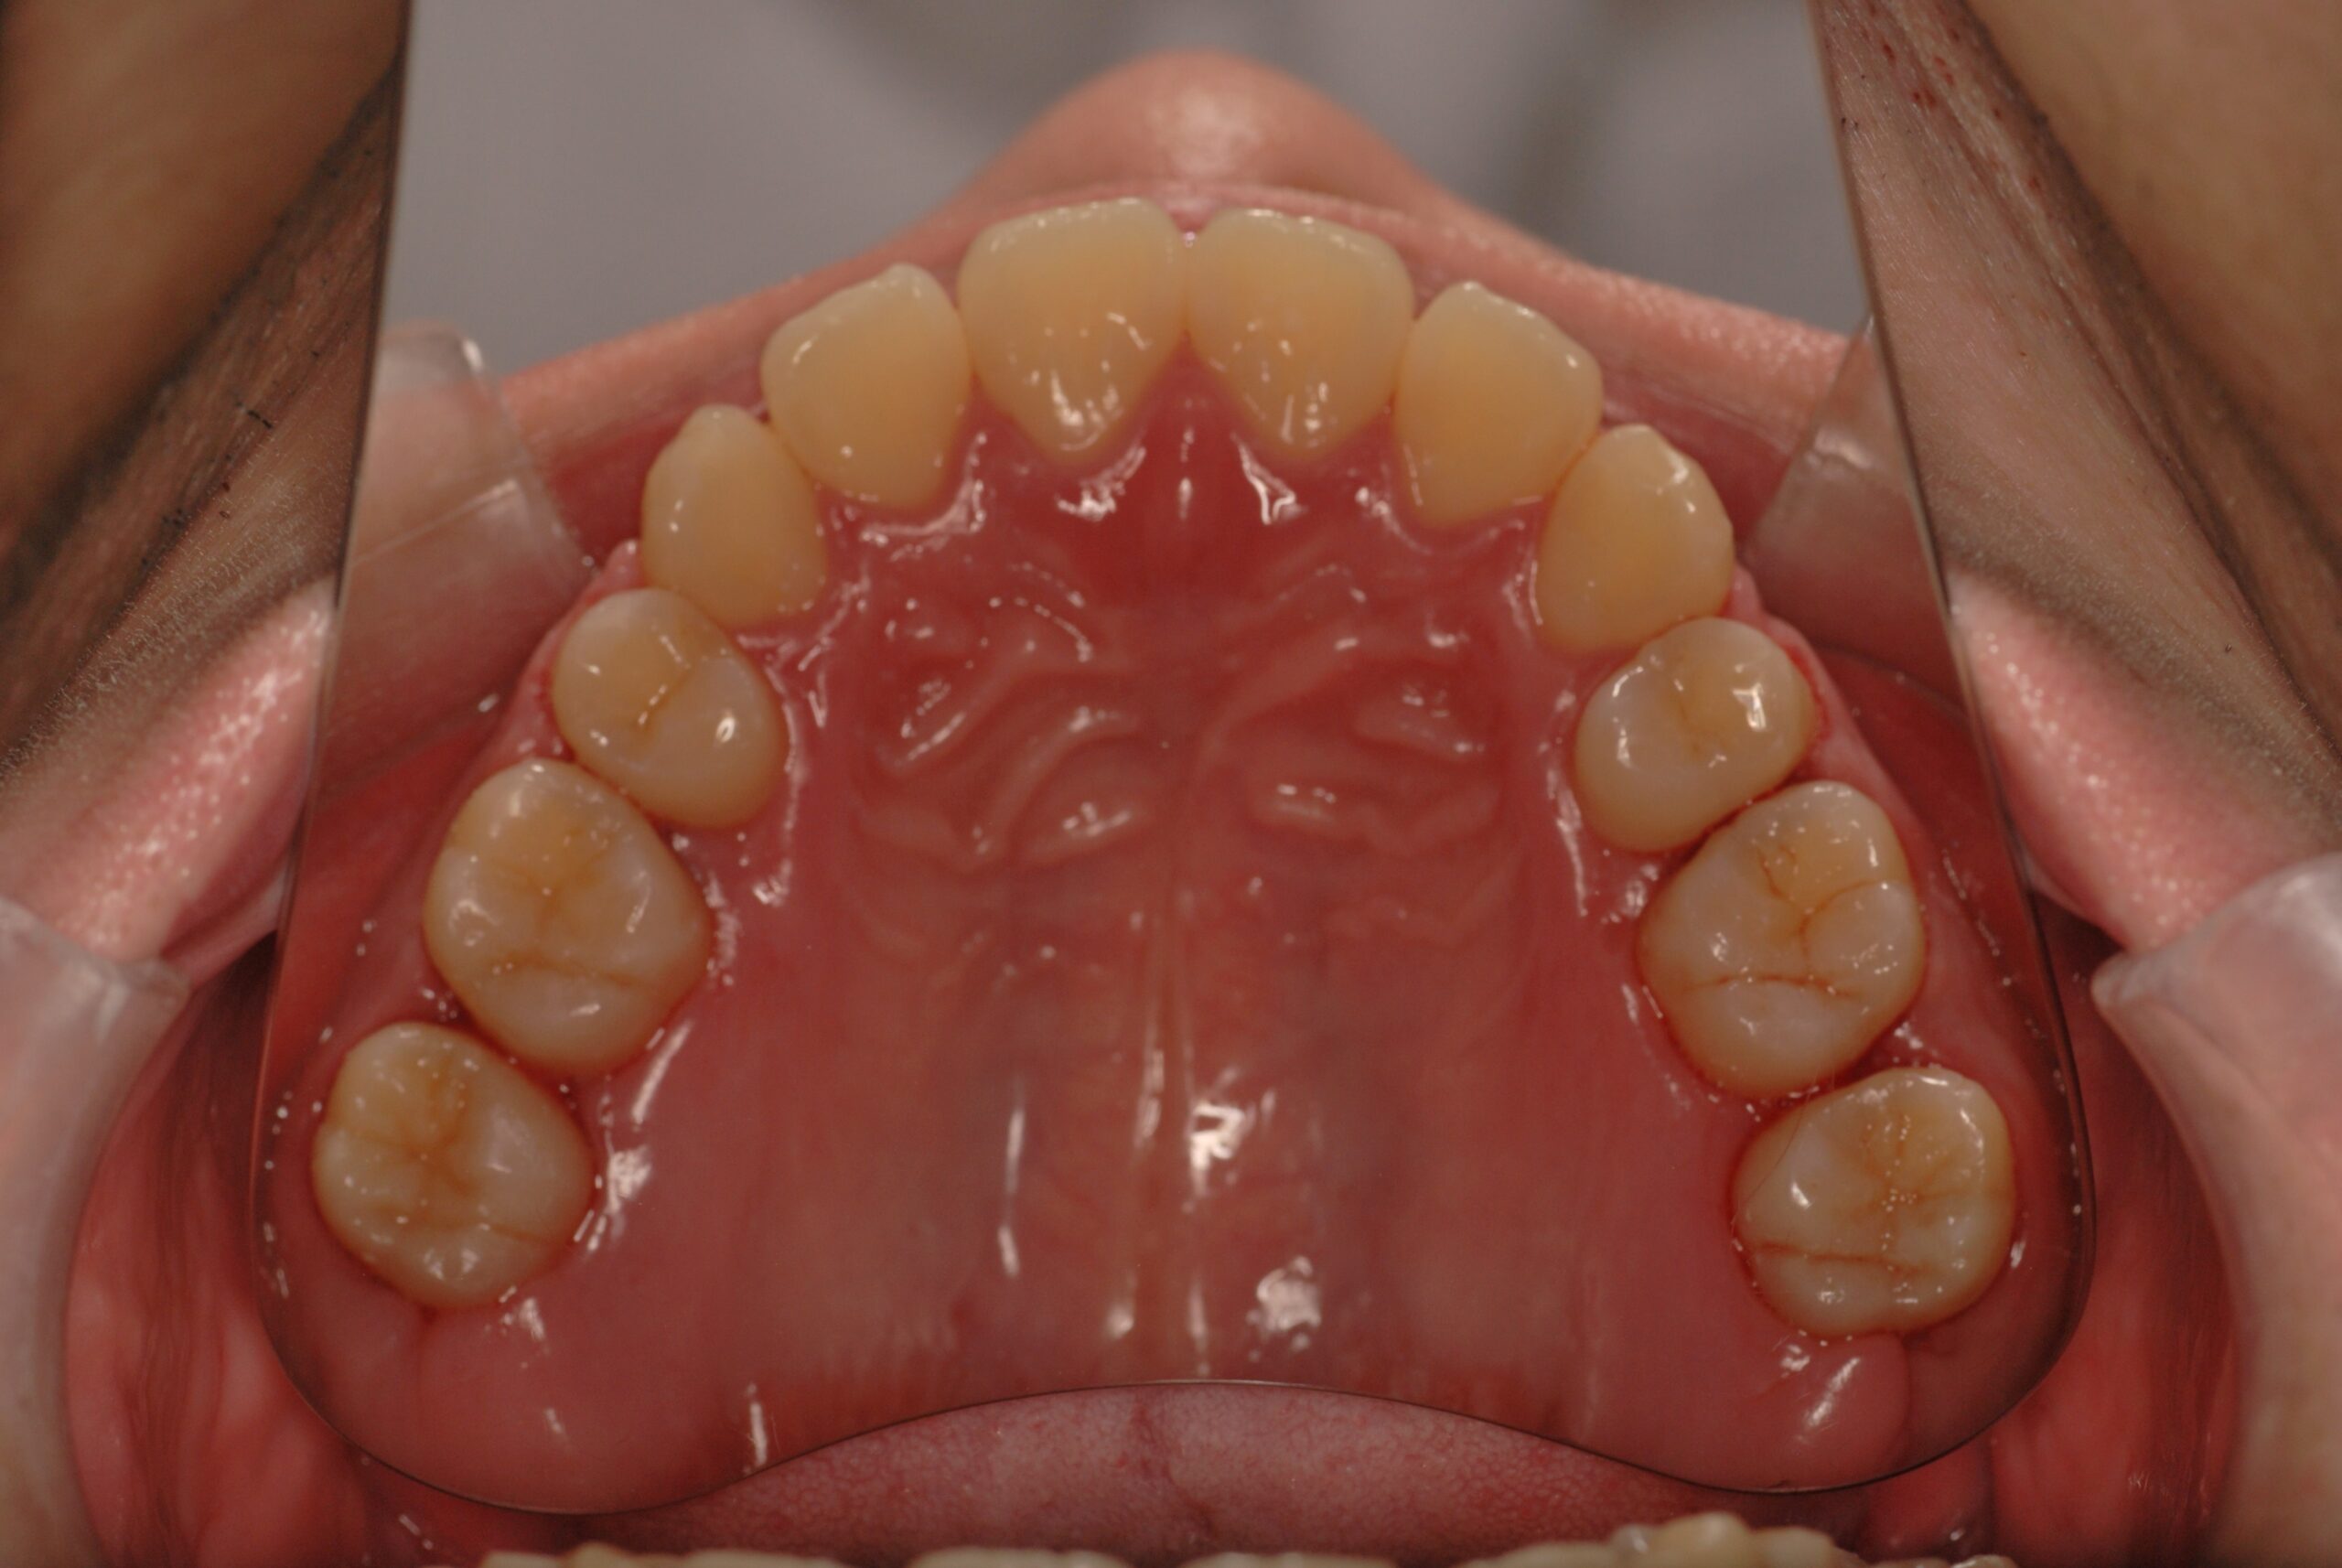

反対咬合(受け口、下顎前突) 叢生

- 骨格性下顎前突症、下顎骨左偏位、叢生、 顎変形症として、外科的矯正術を計画。 叢生、右側第2大臼歯鋏状咬合。 上下顎第一小臼歯を抜歯し、抜歯空隙を利用し叢生を改善し、上下顎それぞれ歯列を整列し、矯正治療中に病院歯科口腔外科にて外科手術(近郊の病院歯科口腔外科にて、口の中から手術、2週間入院)により下顎骨の後退と左偏位の改善をし、適切なオーバージェット、オーバーバイトを付与する。